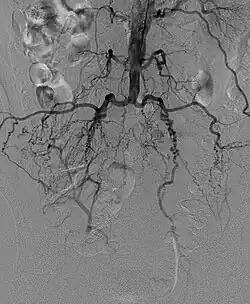

Das Leriche-Syndrom (benannt nach dem französischen Chirurgen René Leriche) ist ein kompletter Verschluss der Aorta distal des Abganges der Nierenarterien, meist vor der Bifurkation in die Beckenarterien. Die Ursachen dafür können Arterienverkalkung (Arteriosklerose), Arterienwandentzündungen (Vaskulitis) sowie Blutgerinnsel (Thrombose/Embolie) sein. In allen Fällen kommt es zu einer Verengung auf der Höhe der Aufzweigung der Bauchschlagader in die Becken-Arterien. Je nachdem, ob die Durchblutungsstörung plötzlich auftritt oder sich langsam entwickelt, kommt es zu kalten Beinen, Schmerzen, erektiler Dysfunktion (Impotenz) und Muskelschwund.

Um eine dauerhafte Schädigung der minderversorgten Gebiete zu vermeiden, muss schnellstmöglich eine Therapie eingeleitet werden. Abhängig von der Ausprägung der Durchblutungsstörungen kommen entweder Katheterverfahren (Angioplastie) oder eine Operation (Bypass oder Y-Prothese) in Betracht.